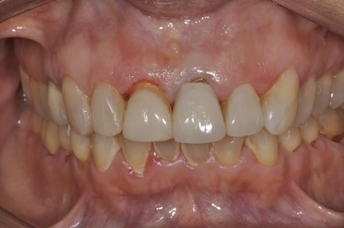

After complete polymerization of the cement, occlusion was checked with the aid of occlusal carbons and the cervical margins were cleaned with an exploratory probe. The cementation interface was finished and polished with abrasive rubbers of different granulations (Figure 12, 13 and 14).

Figure 12 Final aspect of the cemented restorations.

Figure 13 Final aspect of the cemented restorations.

Figure 14 Final aspect of the cemented restorations.